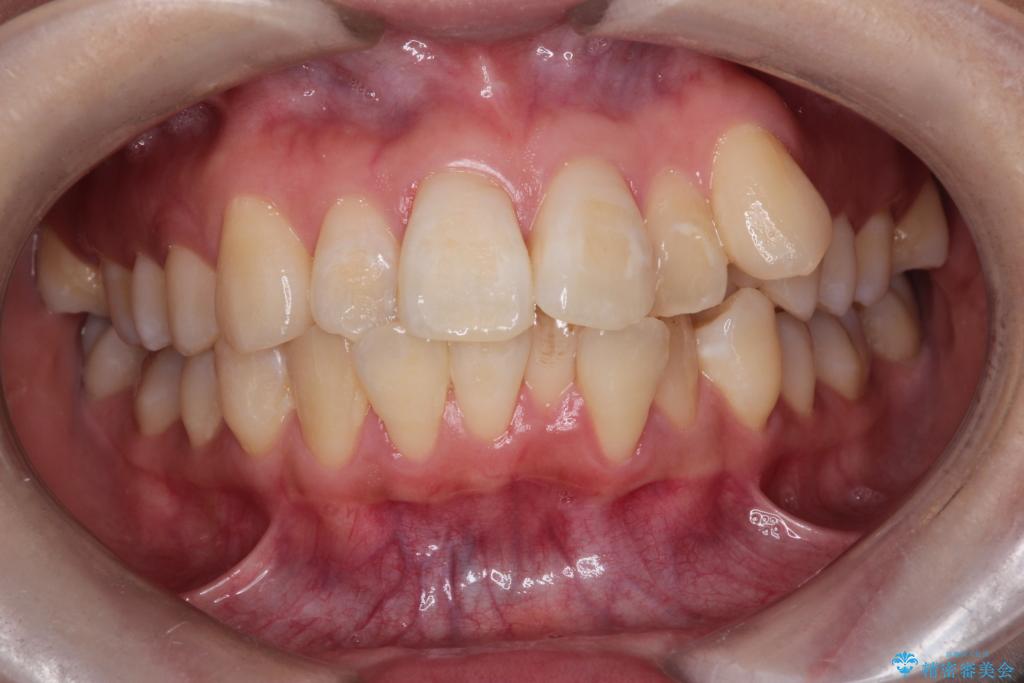

- 八重歯(叢生)と、上下の歯の中心線(正中)がずれていることを主訴にご来院されました。精密な検査の結果、歯列全体のスペースが大幅に不足しており、八重歯を正しい位置に配列し、正中のズレを改善するためには、上下左右の第一小臼歯を抜歯する必要があると診断。装置には、目立ちにくい審美ワイヤーを使用し、見た目を気にせず、機能性と審美性が完璧に整った咬み合わせを目指す治療計画を立案しました。

今回の矯正治療では、まず計画通り上下左右の小臼歯4本を抜歯し、八重歯や正中のズレを解消するための十分なスペースを確保しました。装置には、目立ちにくい白いブラケットとワイヤーを使用した審美ワイヤー矯正を採用。

八重歯: 突出していた八重歯を歯列内に誘導し、デコボコを解消しました。

正中のズレ: 歯を左右対称に移動させることで、上下の歯の中心線を正確に合わせ、顔全体のバランスも改善しました。

治療の結果、長年気にされていた八重歯と正中のズレが解消し、機能的にも整った理想的な歯並びを獲得。目立たない装置で治療を完遂し、自信を持って笑える美しい笑顔を手に入れていただけました。